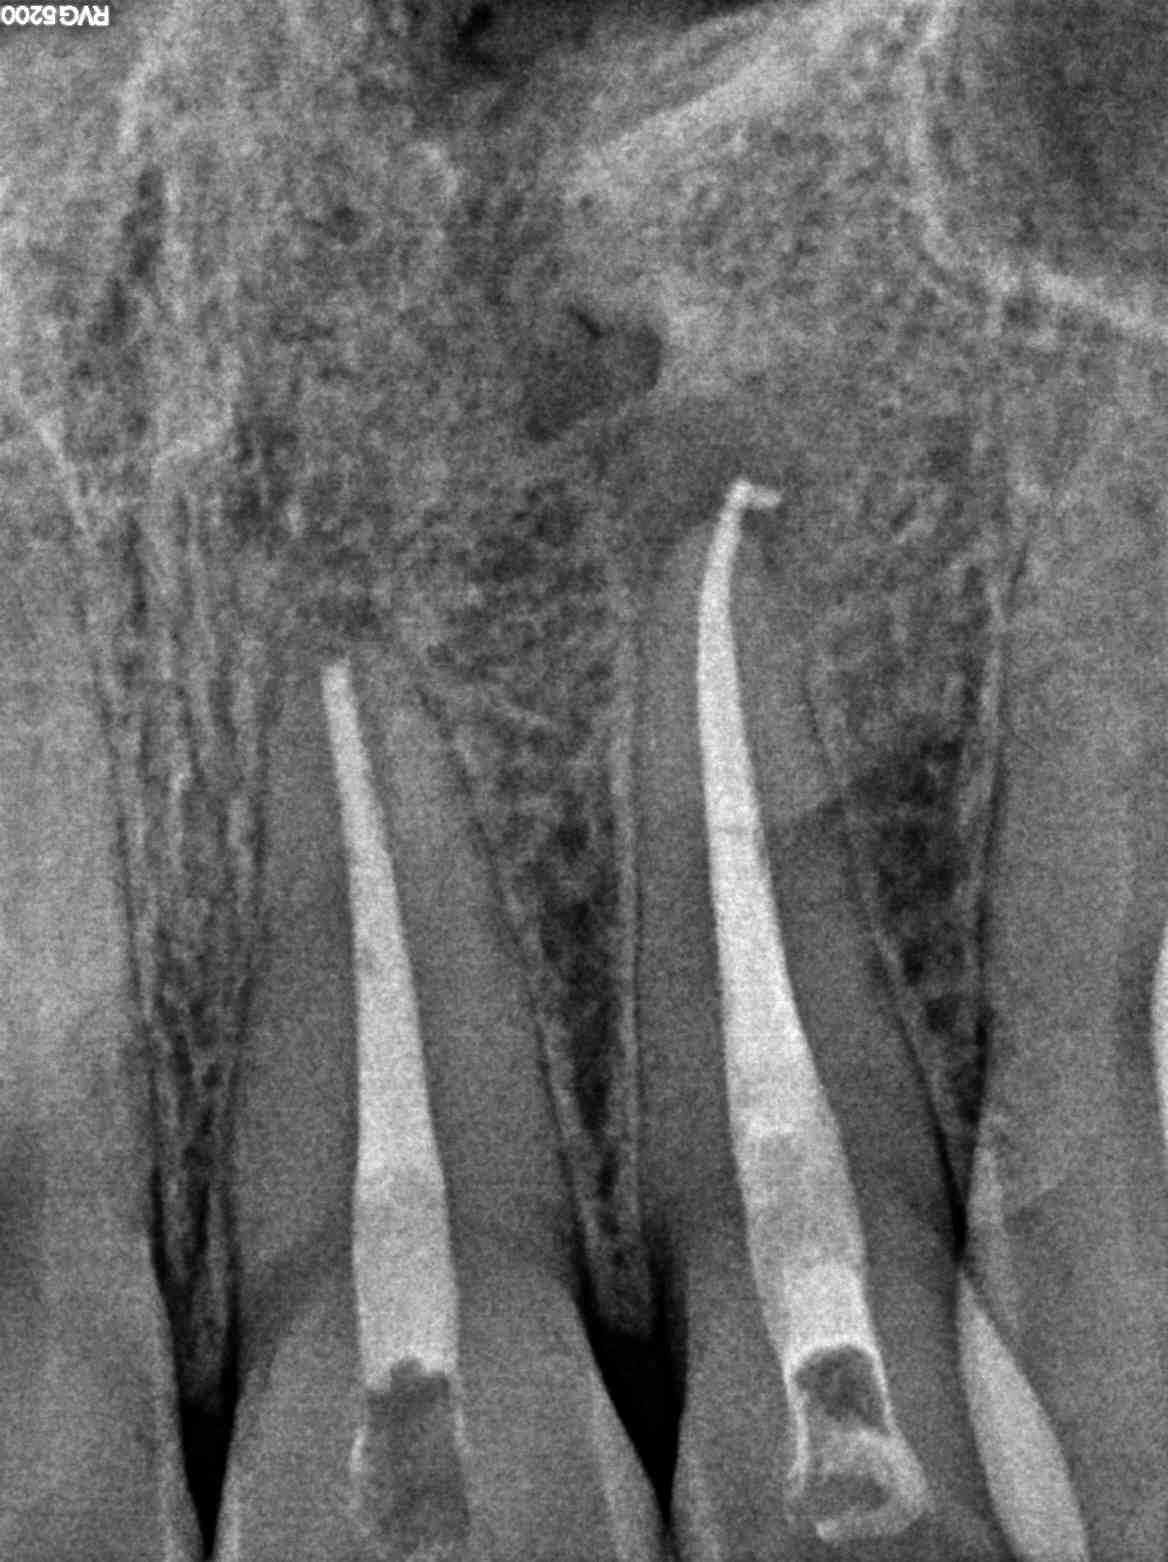

• توضع ملفات دواره صغيرة تقوم بإزالة النسيج الميت والمصاب.

• استخدام مواد التنظيف المطهرة لتنظيف وتطهير تلك القنوات.

•  وأخيرا يتم إضافة الحشو لسد التجاويف في الضرس، ولكن يجب أن يسد الطبيب التجاويف بالكامل حتى لا يدع مجال للبكتيريا أن تنمو.

نقوم باستخدام اجهزة قياس طول القنوات العصبيه الأدق على الإطلاق في العالم حتى لا يخرج حشو العصب أقصر أو أطول من المطلوب.

نستخدم اجهزة حقن حشو العصب السائل الذي يقوم بملأ كل قنوات العصب الرئيسيه والجانبيه بشكل محكم للغايه حتى لا نترك أي فراغات لنمو البكتيريا.

كل الخطوات تتم بإستخدام الميكروسكوب ذو القدره التكبيريه العاليه لضمان اقصى درجات الدقه وايضاً للفحص الدقيق عن أي قنوات فرعيه زائده قد تسبب فشل الحشو بعد ذلك.